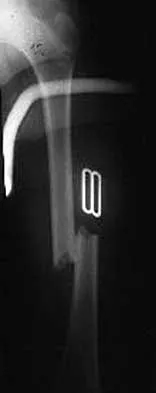

Question 16

Figure 22 shows the radiograph of a 7-year-old boy who underwent retrograde elastic nailing of a femoral shaft fracture. What is the most common problem following this procedure?

Explanation